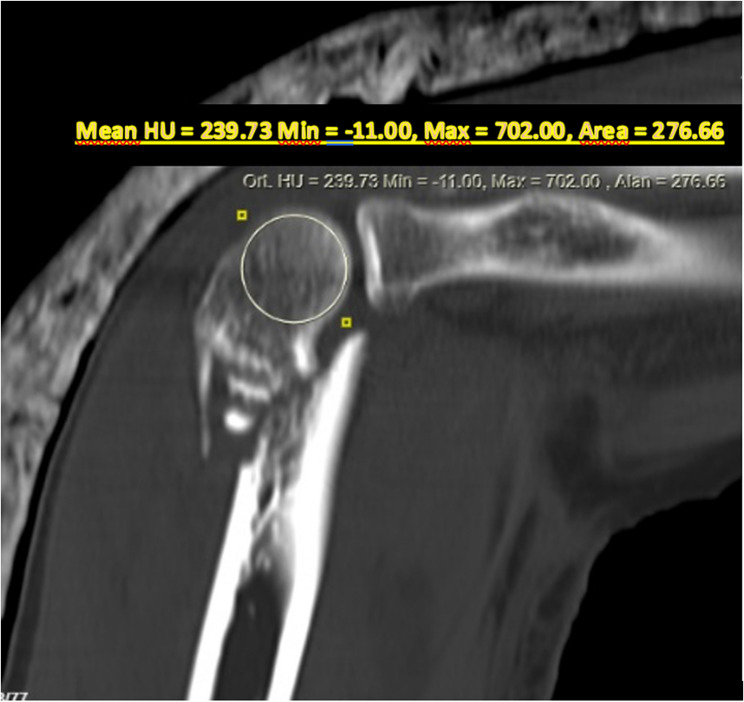

Methods: In this retrospective study, 80 patients over the age of 50 who underwent surgery for AO/OTA type 13-C distal humerus fractures between 2012 and 2022 were analyzed. Patients were categorized into two groups according to the plating technique: parallel(n = 33) or orthogonal(n = 47). Functional and radiological outcomes were compared, including elbow range of motion, Mayo Elbow Performance Score (MEPS), QuickDASH, time to union, complication and reoperation rates, and presence of post-traumatic osteoarthritis. Bone quality was stratified based on HU measurements obtained from preoperative CT scans, specifically from the largest intact slice of the capitellum and trochlea in the sagittal view and from the axial slice just above the proximal fracture line, using a threshold value of 124.5 HU corresponding to the median HU value of the patient cohort. MEPS and QuickDASH were evaluated at the 12-month postoperative follow-up.